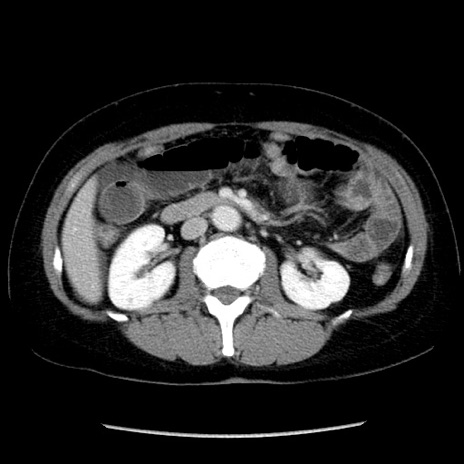

冠状断像

矢状断像